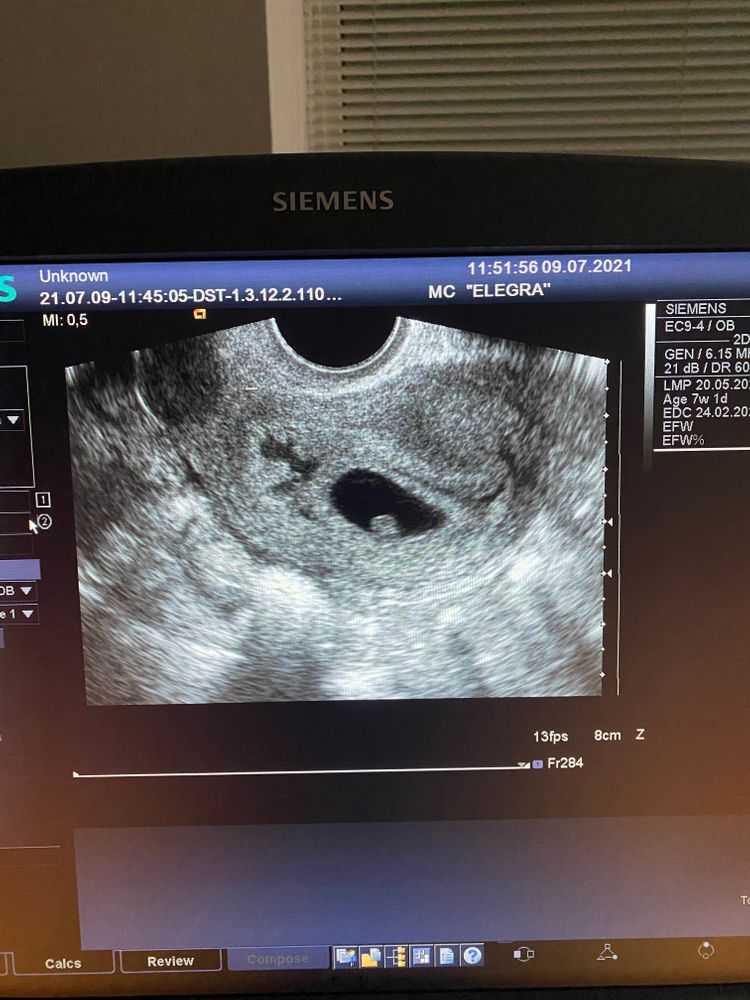

Беременность 4 недели от зачатия (овуляция была поздней, поэтому так удобнее ориентироваться)

На УЗИ сказали, что полость матки расширена, возможно гематома, но типа надо показать своему врачу, как будто она не уверена в этом. Я к своему врачу записана только на 15 июля. сил нет ждать 🙈 может вы подскажете, многие из вас уже лучше гинекологов все знают)

Мне вообще казалось, что полость матки должна расширяться при беременности, может позже, не на моем сроке конечно..

Кровянистых выделений нет.